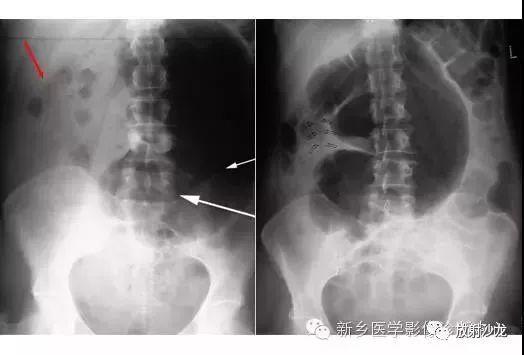

急诊卧位及立位腹平片正常气腹小肠梗阻前哨肠曲

肠梗阻腹部平片图片

肠梗阻腹部平片

肠梗阻腹部平片表现